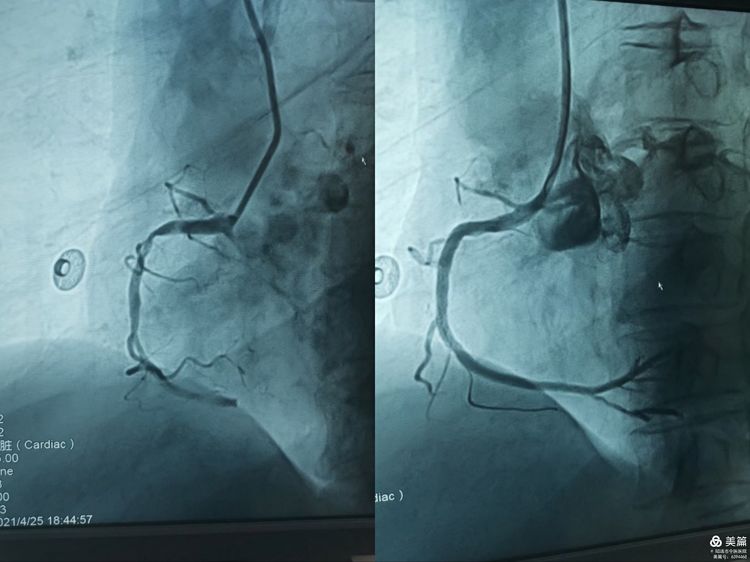

时间就是生命,时间就是心肌 ——心血管病科6小时...

近日,一位66岁女性因突发胸闷到我院心血管病科就诊,经诊断为急性心肌梗死,科室主任王...